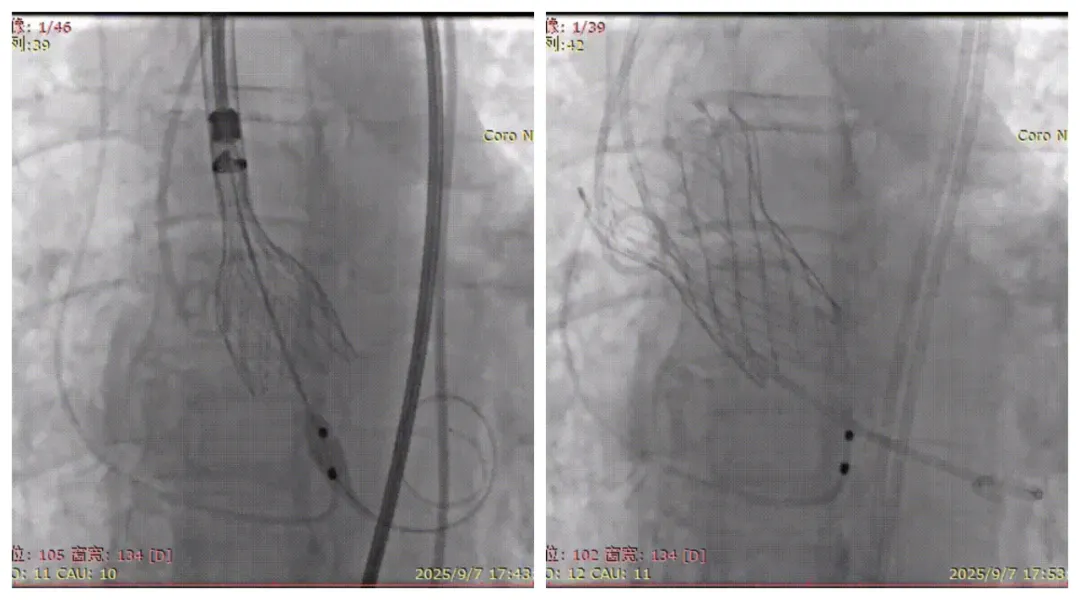

在严重钙化合并横位心的超高危患者手术中,团队创新应用SNARE导管牵拉技术,有效改善输送轨道的同轴性,确保人工瓣膜顺利抵达目标位置。同时,团队选用在处理重度钙化病变中具有优势的VenusA瓣膜系统,显著降低了瓣膜膨胀不全、移位及冠脉受压等并发症风险,为手术成功奠定坚实基础。

在重度主动脉瓣反流合并四叶瓣畸形患者手术中,团队依托术前CT三维重建提供的精准数据,精心选择带有外裙边设计的TaurusOne瓣膜,以尽可能减少术后可能出现的瓣周漏。在释放过程中,术者凭借毫米级的精细操控和多年临床经验,将人工瓣膜精准锚定于“黄金区域”。术后即刻经食道超声确认:人工瓣膜位置完美,反流完全消失,且未对心脏传导系统造成影响。